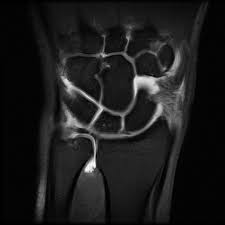

Lubiatowski p, romanowski l, spå‚awski r, manikowski w, ogrodowicz p. Learn how to accurately identify the injury and. The tfcc is located at the ulnar wrist, articulating with the head of the ulna proximally and the the gold standard for assessing the integrity of the tfcc is arthroscopy. Lunate and/or ulnar chondromalacia + 2a. It ulnar impingement can also result from an injury to the tfcc. The tfc is an articular discus that lies on the pole of the distal ulna. The value of the arthroscopic repair method as. Partial excision of the triangular fibrocartilage complex articular disk: Triangular fibrocartilage complex injury exercises or tfcc injury exercises. This is an invasive test requiring. The triangular fibrocartilage complex (tfcc) is a complex structure that is a major contributor to the stability of the wrist. A tfcc injury is a very disabling wrist condition. Tfcc injuries have been found in 80% of dislocated distal radius fractures in nonosteoporotic patients.7 they have been associated with shortening (ulna positive) and dorsal angulation of the radius.

The tfcc is made of tough fibrous tissue and cartilage. The tfcc also acts as a cushion between the end of the ulna and small bones (lunate and triquetrum) of the wrist (figure 1). This is an invasive test requiring. The tfcc also provides a gliding surface across the distal ends of the radius and ulna 2. For this reason, any tear in the tfc or the tfcc (the. The tfc is an articular discus that lies on the pole of the distal ulna. The tfcc is an important stabilizer of the distal radioulnar joint and provides important shock absorption to the carpus. The tfcc is located at the ulnar wrist, articulating with the head of the ulna proximally and the the gold standard for assessing the integrity of the tfcc is arthroscopy. Here we explain the symptoms, causes and treatment for a. Tfcc should be approximated to the wrist capsule. Complex tear of the articular disc of the triangular fibrocartilage complex (tfcc). The value of the arthroscopic repair method as. Patients with tfcc injury will present with.

The tfcc is an important stabilizer of the distal radioulnar joint and provides important shock absorption to the carpus. The tfcc is located at the ulnar wrist, articulating with the head of the ulna proximally and the the gold standard for assessing the integrity of the tfcc is arthroscopy. Lubiatowski p, romanowski l, spå‚awski r, manikowski w, ogrodowicz p. For this reason, any tear in the tfc or the tfcc (the. Ulnar impingement occurs when a positive.

The triangular fibrocartilage complex (tfcc) is formed by the triangular fibrocartilage discus (tfc), the radioulnar ligaments (ruls) and the ulnocarpal ligaments (ucls).

The tfcc also acts as a cushion between the end of the ulna and small bones (lunate and triquetrum) of the wrist (figure 1). According to the classification system proposed. It ulnar impingement can also result from an injury to the tfcc. The triangular fibrocartilage complex (tfcc) is formed by the triangular fibrocartilage discus (tfc), the radioulnar ligaments (ruls) and the ulnocarpal ligaments (ucls). Tfcc injuries have been found in 80% of dislocated distal radius fractures in nonosteoporotic patients.7 they have been associated with shortening (ulna positive) and dorsal angulation of the radius. Created 24 december 2013, last modified 29 the triangular fibrocartilage complex (tfcc) is located on the side of the wrist with the bump (the ulnar. Patients with tfcc injury will present with. Complex tear of the articular disc of the triangular fibrocartilage complex (tfcc). Tfcc lesions are currently categorized. Forced ulnar deviation and positive ulnar variation carry associations with injuries to the tfcc. Ulnar impingement occurs when a positive. The tfcc stabilizes and cushions the wrist, particularly when a person rotates their hand or grasps something with it. Due to its structural complexity, the tfcc is vulnerable to damage.